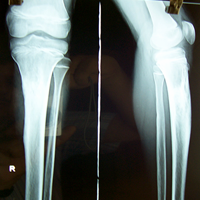

Case:3 Ewings Tibia

Pre-Op

Post-Op